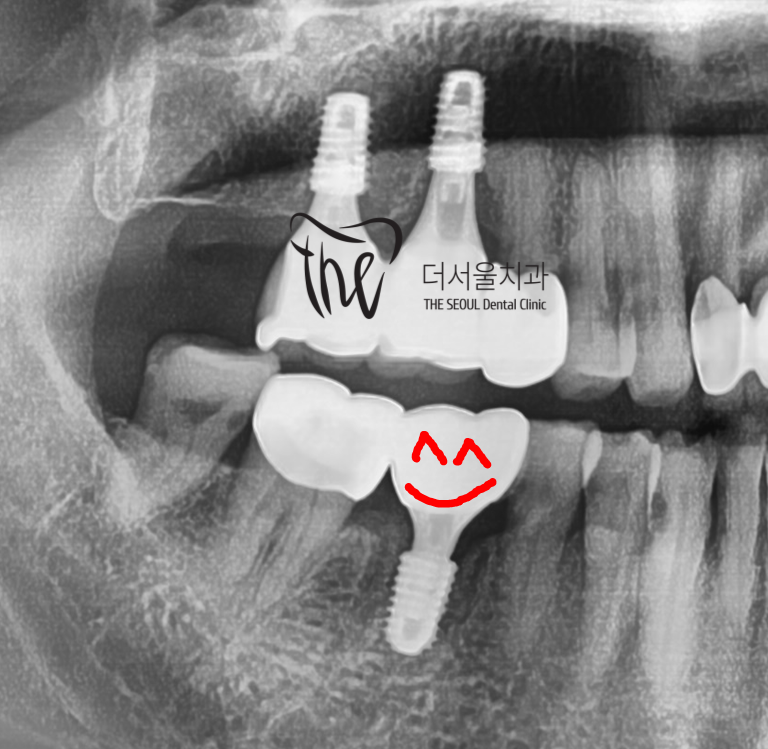

시간이 지나, 골 화가 다 되었을 때는

지르코니아 크라운을 연결해드리면서

모든 치료는 끝나게 됩니다.